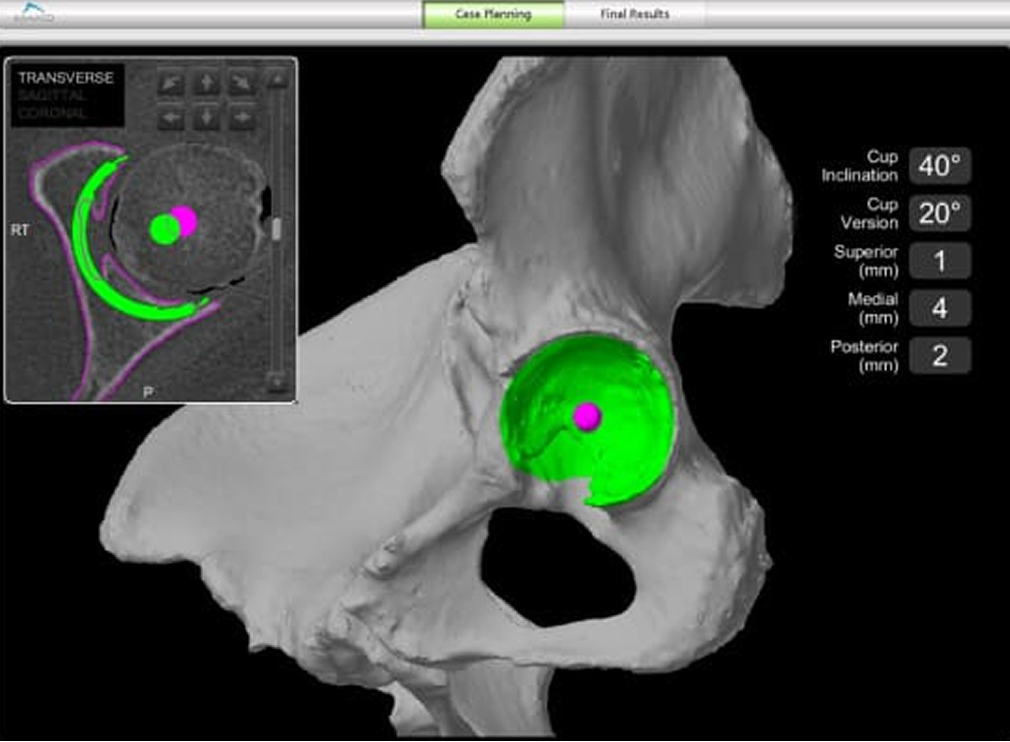

CT画像をもとに作成された三次元画像で手術計画を行い、インプラントサイズ、設置位置、削る深さや角度を決定します。 THAでは骨盤をリーミングしてカップ設置する際、TKAやUKAでは骨切りを行う際にロボティックアームが術者をサポートします。 術前計画にはない角度や深さを削ろうとすると制御がかかり、ロボティックアームが止まるシステムになっています。 身近なものに例えると車の自動ブレーキのようなもので、計画通りの手術を行うことが可能となりました。

• CT画像をもとに作成した三次元像を用いた手術計画

• ロボティックアームを用いて骨盤(臼蓋)の表面を整えます。

• ロボティックアームを用いてインプラントを設置します。